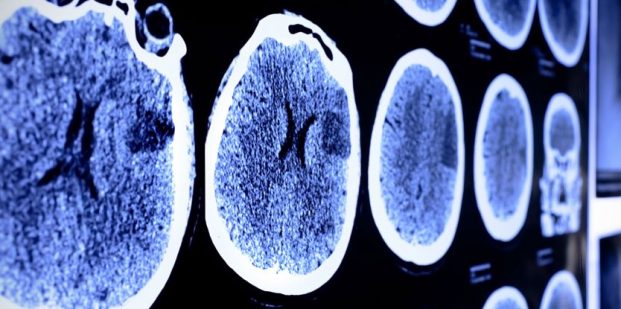

بهبود آثار سکته مغزی با داروی جدید

به گزارش نوروسافاری از ساینس، سکته مغزی به دلیل کمبود اکسیژن در اثر مسدود شدن یا پارگی رگ های خونی رخ می‌دهد. مغز قادر به ترمیم سلول‌های عصبی مرده نیست؛ اما با استفاده از فیزیوتراپی که منجر به اتصال مجدد برخی از سلول‌های سالم می‌شود، می‌توان بخشی از کارآیی مغز را مجددا به دست آورد.

اکنون محققان داروی جدیدی را شناسایی کردند که موجب بهبود فرآیند اتصال مجدد سلول‌ها در مغز شده و در نتیجه عملکردهای حرکتی فرد مبتلا به سکته را بهبود می‌دهد.